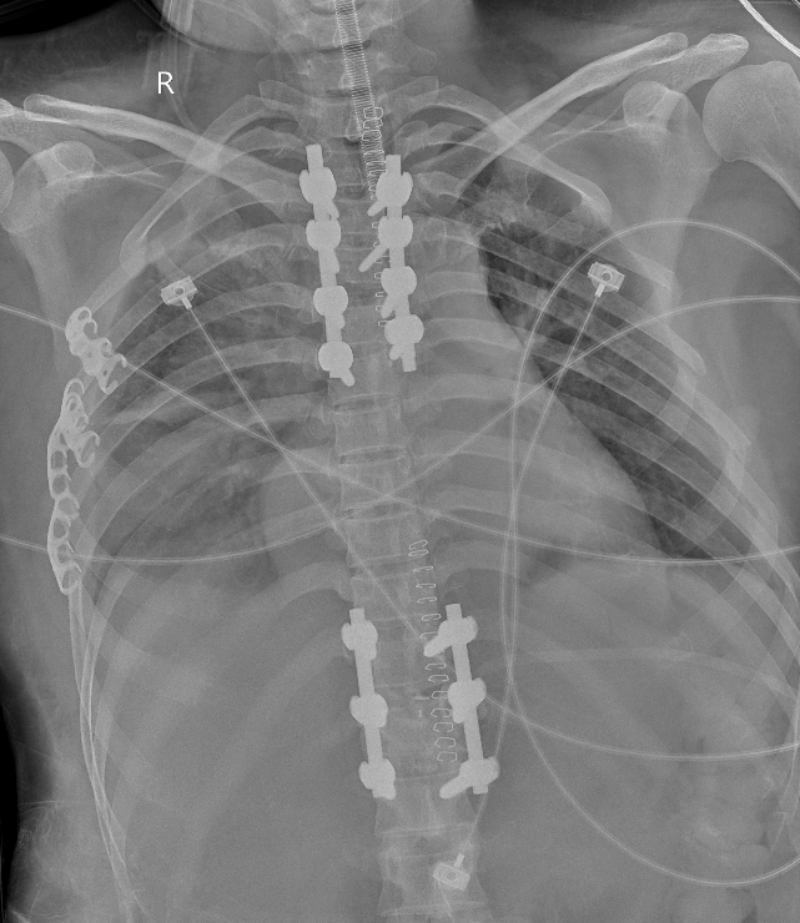

姚仕奮主任團隊對該患者病情展開多次討論,為其制定了詳細的手術方案,推演手術中每個風險環節和應對預案,2024年4月19日,在麻醉科孫岸靈主任、陳蓮主麻醉師的保駕護航下,姚仕奮主任團隊順利為患者行后路胸椎4椎體爆裂性骨折伴脫位切開復位、椎管擴大減壓、椎弓根釘棒系統內固定、橫突間植骨融合術+后路胸12椎體爆裂性骨折切開復位、胸11-12椎板部分切除、椎管擴大減壓、椎間植骨融合、椎弓根釘棒系統內固定、橫突間植骨融合術,手術過程順利,胸4骨折脫位復位良好,內固定在位,術中椎管充分減壓,解除壓迫,術后安返重癥醫學科,繼續在重癥醫學科監護治療。

文章配圖

△ 術后復查見骨折脫位復位良好,內固定在位。